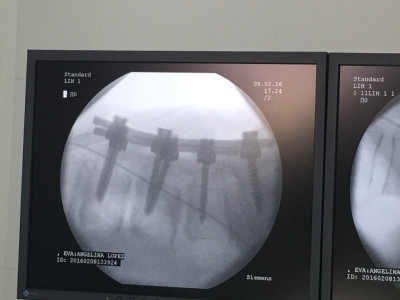

Cirugía endoscópica de columna e instrumentación

Envíado por Dr. Hugo Enrique Castro Cordero